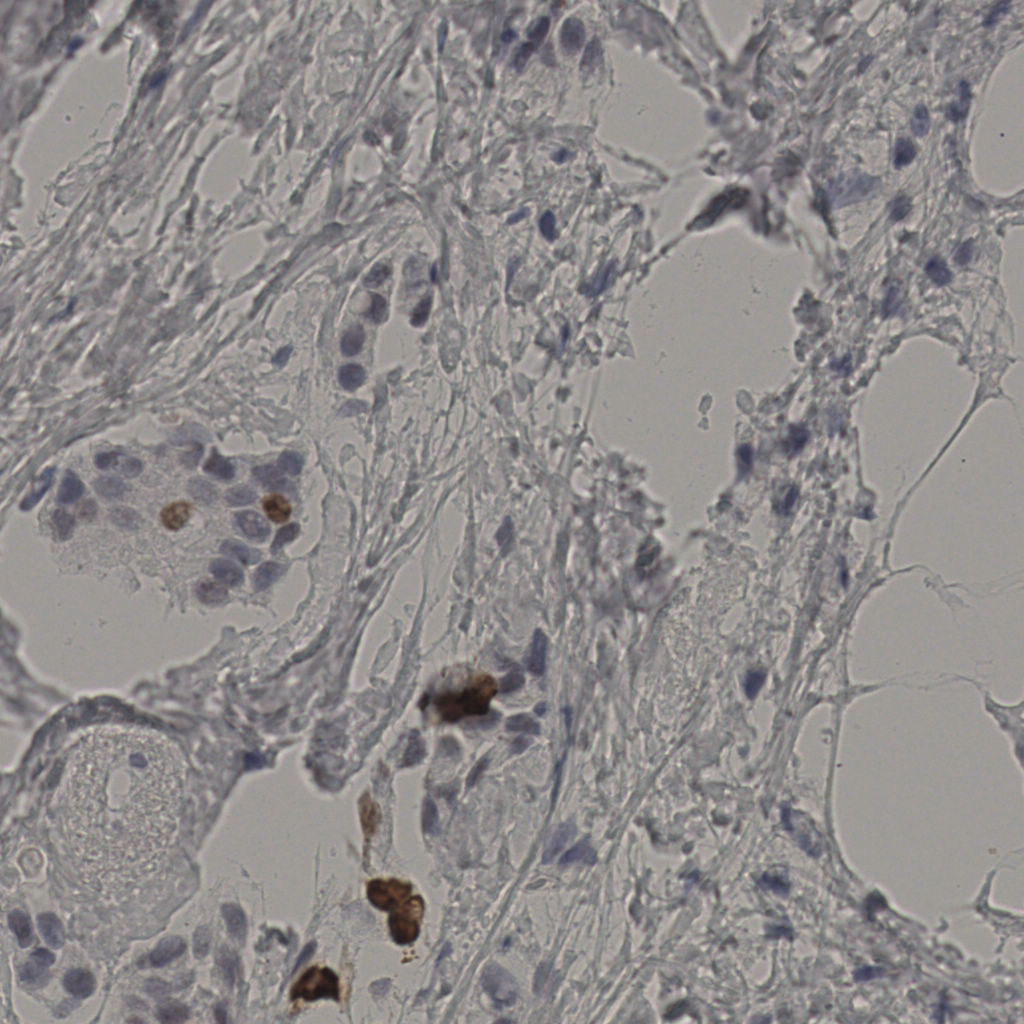

slice_37_8_x33152_y7168.png

slice_37_8_x33152...